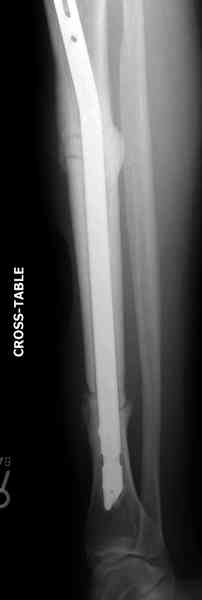

Недавно на нашей ежемесячной Morbidity&Mortality conference мы

разбирали похожий случай, ложный сустав большеберцовой кости после

резекции опухоли.

Оперирован в военном госпитале с заменой сегмента аллокостью

большеберцовой кости и после демобилизации явился для постоянного

наблюдения по месту жительства.

Наши имели проблему со сращением, пришлось им сделать динамизацию,

дополнительную аутопластику.

Снимки представлены.

Имя     : 2 adamantioma lat preop.jpg